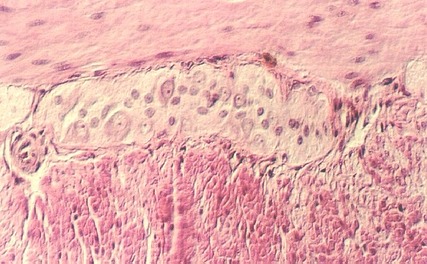

Muscularis Externa and Auerbach's plexus

Identify the MUSCULARIS EXTERNA in slide 53. This consists of inner circular and outer longitudinal layers. Auerbach's plexus lies between the muscle layers, as shown in the following photographs.